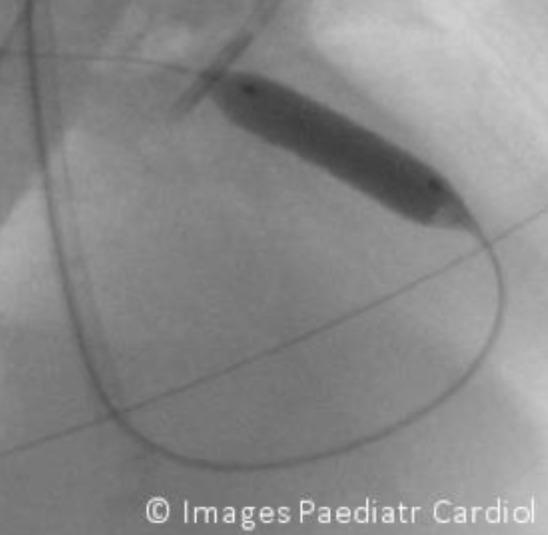

Right ventricular outflow tract stenting - effective palliation for Fallot's tetralogy.

Images Paediatr Cardiol. 2015 Jul-Sep;17(3):3-10.